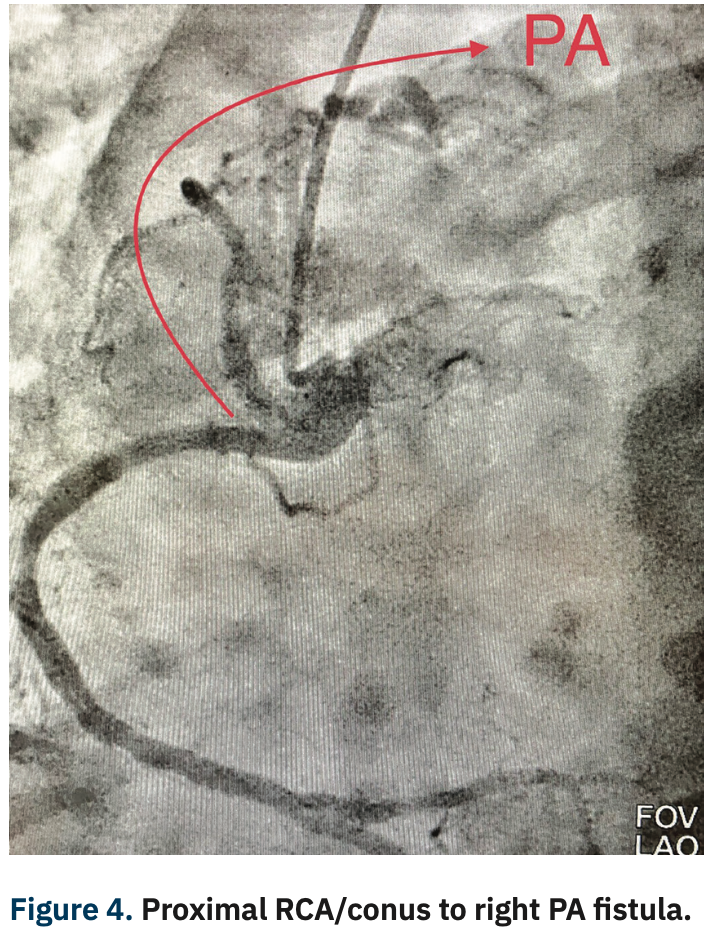

She underwent a coronary angiogram via right radial artery approach utilizing the hyper adducted right radial artery (HARRA) method3 (Figure 1), with angiography showing a normal left main and left circumflex coronary artery. There was a 50% stenosis in the mid LAD and mid right coronary arteries (Figure 2). Angiography also revealed a fistula connection between the proximal LAD and the left pulmonary artery, as well as the conus branch of the RCA and right pulmonary artery (Figures 3-5).